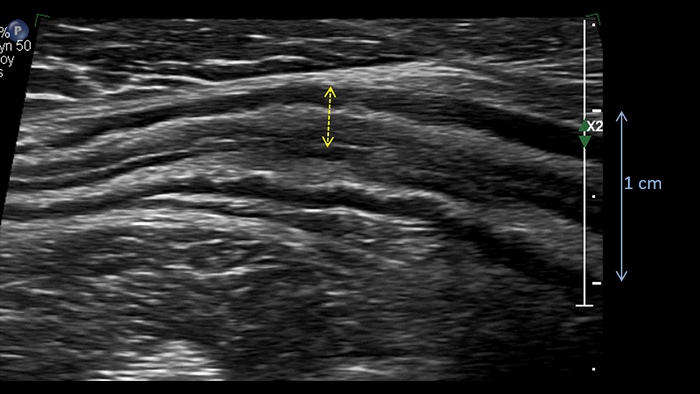

Ces images précises des lésions des couches pariétales forment la base de l’interprétation des changements induits par l’inflammation des parois intestinales et par conséquent de la différenciation entre la maladie de Crohn et la rectocolite hémorragique. L’exploration avec la technologie MFI (MicroFlow Imaging) constitue la deuxième étape. Il s’agit de reconnaître l’aspect de l’hypervascularisation induite par des épisodes inflammatoires actifs. La paroi intestinale normale semble comporter peu de microvaisseaux détectables, uniquement à l’interface de la muqueuse et de la sous-muqueuse, et dans le tissu adipeux mésentérique adjacent. Inversement, la paroi inflammatoire présente de nombreux microvaisseaux. La distinction entre les images d’artefacts de mouvement et les microvaisseaux circulants est alors un point essentiel nécessitant un ajustement parfait des paramètres de détection des micro-flux (voir les boucles, diapositive 8). La comparaison des 4 images suivantes de la maladie de Crohn met en évidence des différences claires qui devraient être interprétées comme étant représentatives des différents états inflammatoires. L’image 1 ne comporte aucun vaisseau visible, ce qui correspond probablement à une absence d’activité. L’image 2 présente quelques vaisseaux ; nous pouvons en conclure que cela correspond à une activité modérée. L’image 3 comporte un plus grand nombre de vaisseaux, signe probable d’une activité intense. L’image 4 présente encore plus de vaisseaux de type pulsatile, ce qui évoque probablement une activité très intense.

Few vessels moderate activity ?